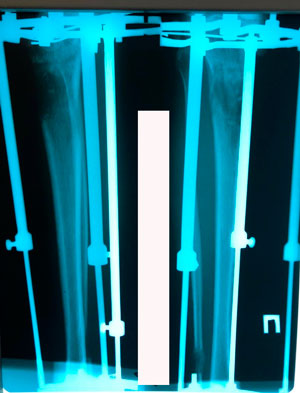

рентген в процессе удлинения

рентген в 90 дней

удлинение на 4,5 см

продолжаем сращение